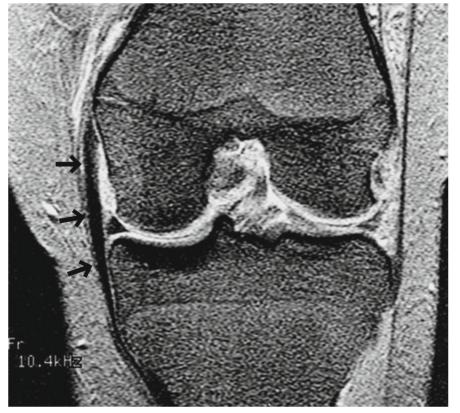

在2-3级MCL撕裂中,将会看到由于水肿和血肿导致的纤维不连续和信号异常(图5.8和5.9)。

- 水肿的变化可能不仅限于MCL本身,还可能扩展到周围的内侧支持带和股内侧肌(图5.8)。

图5.8的2级撕裂(部分撕裂)。一个40多岁的男性。(a)冠状面和(b)轴位FS PDWI显示MCL表层水肿肿胀和不连续(箭头)。水肿的改变也可见于内侧支持带(b中箭头)和股内侧肌(a 中箭头箭头)